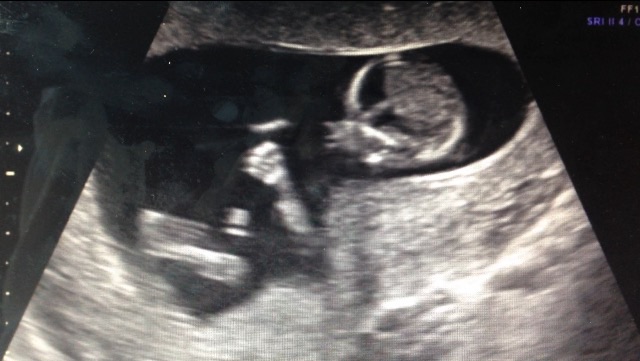

This is pretty interesting! According to this theory, a girl will have a more rounded forehead and a boy will have more of a slope forehead. This is my sonogram at 14 weeks. And the skull looks to be more sloped straight down then rounded and bulb like... but it's still too early to tell. What do you ladies think? And has anyone else ever looked into it?

when pregnant with my other kids, and have said "the profile just looks like a ___(insert boy/girl here____!" So this theory excites me and could definitely be plausible. I should dig out the albums and look to see if it holds true to my kids.